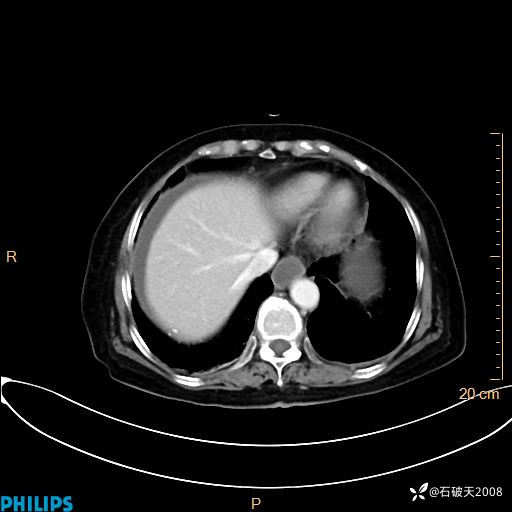

女82岁 主 诉:腹痛半月,加重3天

现病史:半月前患者无明显诱因出现腹痛,上腹部、下腹部间断隐痛,进食后明显,腹胀,大便干,无反酸、烧心,无恶心、呕吐,无腹泻、发热,无咳嗽、咳痰,无心慌、胸闷、无头痛、头晕,无粘液脓血便等症状,患者就诊XXXX医院,给予中草药治疗(具体药物不详)治疗,效差,3天前患者腹痛较前加重,上腹部、下腹部间断隐痛,伴间断性绞痛,今为求进一步诊治来诊我院,门诊以“腹痛”为诊断收住院,自发病来神志清,精神差,饮食差,睡眠一般,小便正常,体重无明显变化。

静脉期